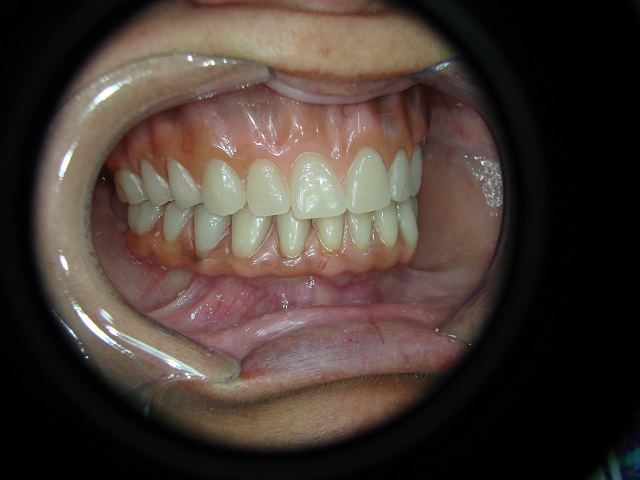

Caso Inicial